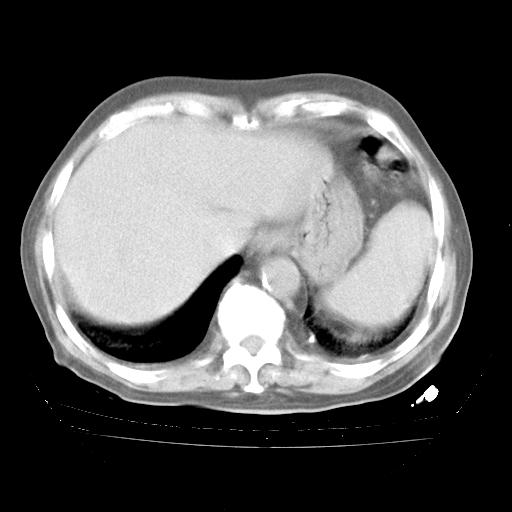

4月28日肺部CT——再次出现类似去年5月9日——透光度降低,“间质性”改变。

4月28日肺部CT